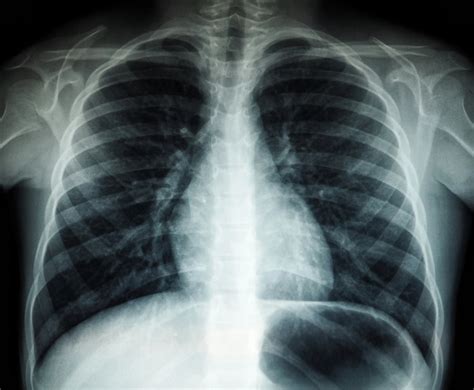

Nėštumo metu pakankamai saugiais laikomi mamos galūnių, dantų, galvos ir krūtinės ląstos rentgeno tyrimai. Tačiau net ir šiais atvejiais, jei numatomas bet koks tyrimas, visada gydytojui reikia pranešti, kad esate nėščia arba galite lauktis. Jei nėštumo metu jums bus atliekama galūnių, galvos ar kaklo srities rentgenograma, gydymo įstaigos personalas duos švino prijuostę. Gydytojas taip pat gali rekomenduoti kitą diagnostinį metodą.

Pavojingesnės yra tos rentgenogramos, kurios atliekamos pilvo ir ypač dubens srityje. Kompiuterinės tomografijos (KT) metu spindulių dozė yra žymiai didesnė nei paprasto rentgeno tyrimo metu, todėl KT tyrimai, ypač pirmosiomis nėštumo savaitėmis, kelia didesnį pavojų. Tiesiosios žarnos tyrimo metu, kai naudojama bario klizma, taip pat atliekama rentgeno nuotraukų serija, kuri gali būti rizikinga.

| Galūnės, galva, krūtinės ląsta, dantys | Paprastai laikomi pakankamai saugiais, su papildoma apsauga. |

| Pilvas, dubens sritis | Reikalauja ypatingo atsargumo, ypač pirmąjį trimestrą. |

| Kompiuterinė tomografija (KT) | Didelė spinduliuotės dozė, didesnė rizika. |